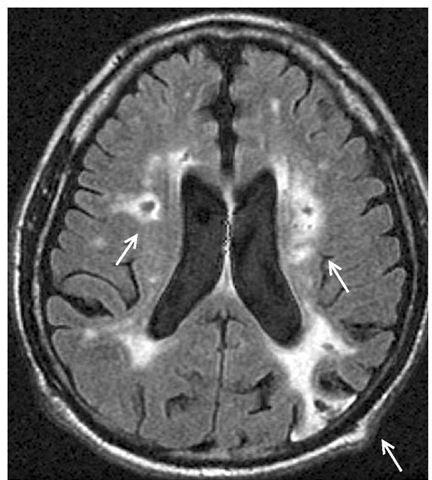

相关图片